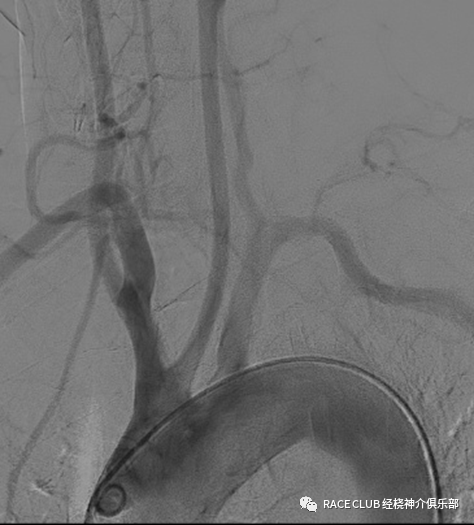

主动脉弓造影

用泥鳅导丝将猪尾导管导入升主动脉,抽出导丝,接注射器

摆好位置,一般左斜45°,下端露出导管头

接高压连接管

注意看弓形态、各个开口大致位置、走形,特别注意右侧锁骨下动脉